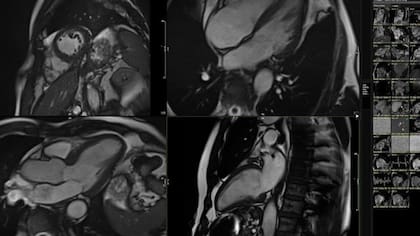

El proceso implicó realizarme una resonancia magnética (MRI) de mi corazón después de algo de ejercicio ligero. Los primeros signos de envejecimiento prematuro pueden ser tan sutiles que incluso los cardiólogos expertos son incapaces de detectarlos.

Pero, la herramienta de inteligencia artificial sí puede, porque contiene imágenes de 40.000 personas con diferentes condiciones de salud cardíaca junto con sus resultados de salud.

El sistema analizó cientos de pequeños detalles en el movimiento 3D de mi resonancia magnética y los comparó con los de 5000 personas de distintas edades que habían llevado estilos de vida saludables.